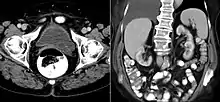

A ureterocele is a congenital abnormality found in the ureter. In this condition the distal ureter balloons at its opening into the bladder, forming a sac-like pouch. It is most often associated with a duplicated collection system, where two ureters drain their respective kidney instead of one. Simple ureterocele, where the condition involves only a single ureter, represents only twenty percent of cases.

Since the advent of the ultrasound, most ureteroceles are diagnosed prenatally. The pediatric and adult conditions are often found incidentally, i.e. through diagnostic imaging performed for unrelated reasons.

IVU-shows Adder head appearance or Cobra head appearance. Cystoscopy-shows translucent cyst which is thin walled surrounding ureteric orifice